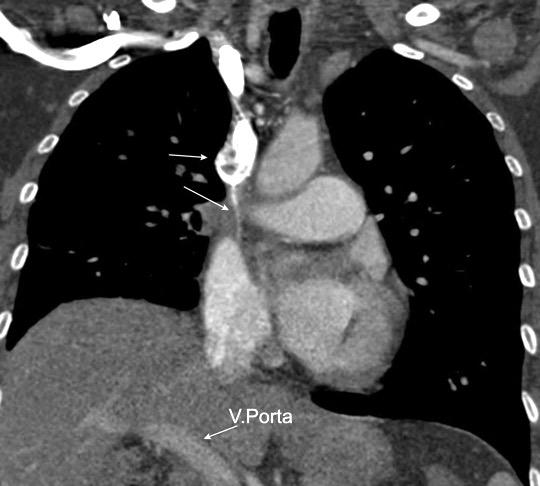

1. Obstrucción por encima de la V Ácigos. (La sangre llega al corazón a través de ella)

2. Obstrucción con participación de la V. Ácigos. (La sangre utiliza otras alternativas para llegar al corazón vía VCI).

Participación de la V. Ácigos como vía principal para llegar a la VCI.